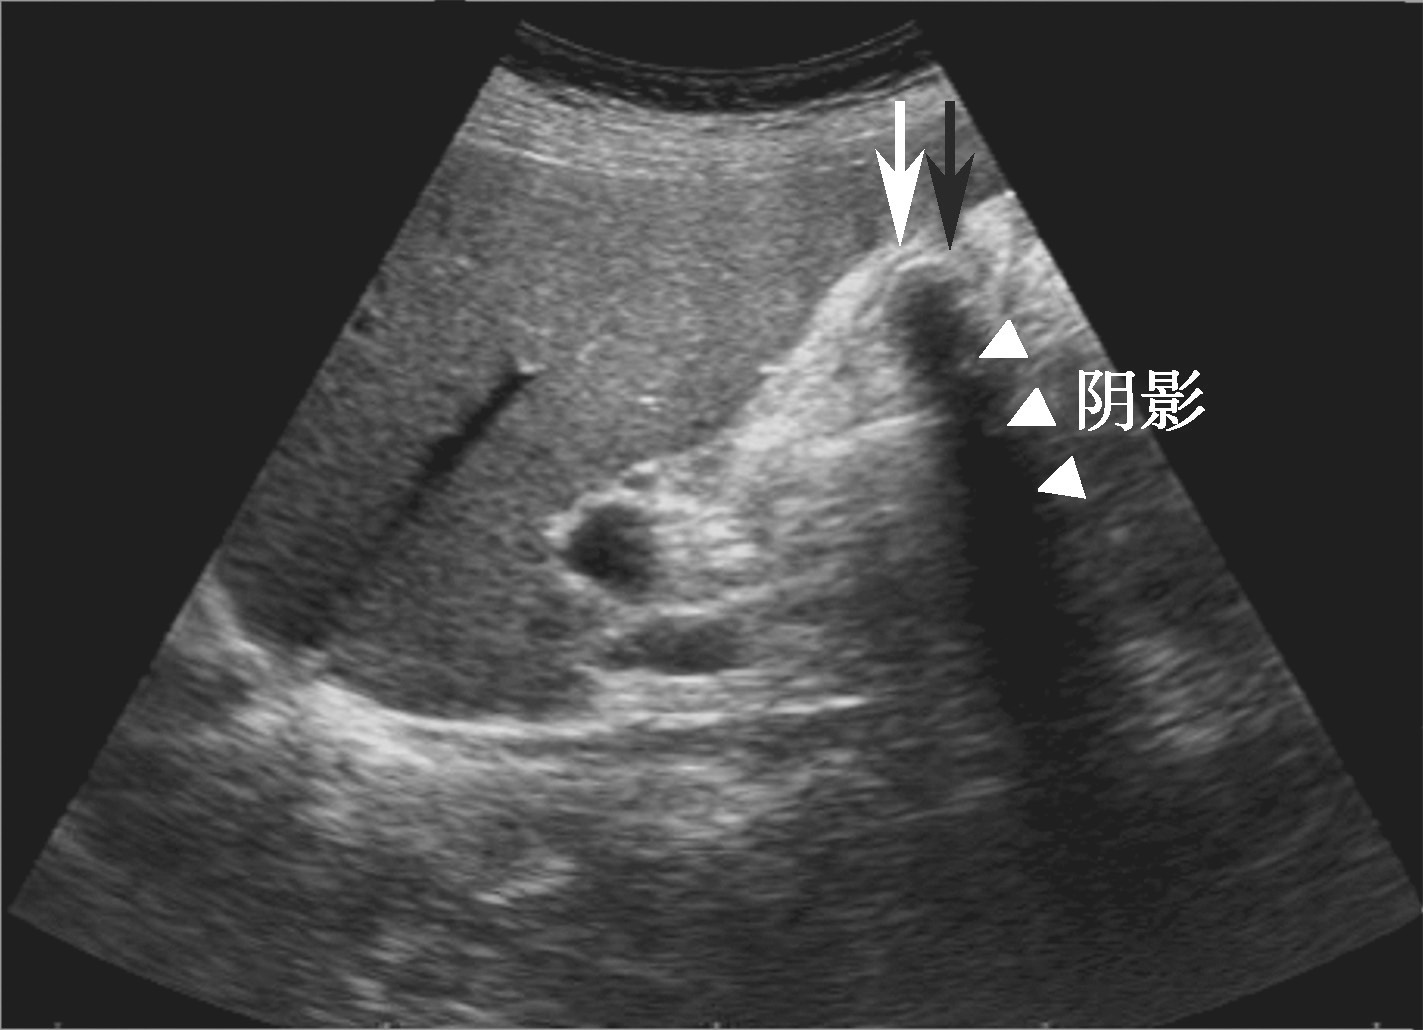

①胆囊萎缩或正常大小,胆囊壁不光滑,回声增高,可弥漫性增厚。②合并胆囊结石时,可见结石声像特征。但胆囊内充满结石时,表现为特征性的囊壁——结石——声影三合征,即WES征(图2-2-2)。③胆囊收缩功能减退。

图2-2-2 胆囊充满型结石WES征

白色箭头为胆囊壁,黑色箭头为结石强回声,三角箭头为结石声影